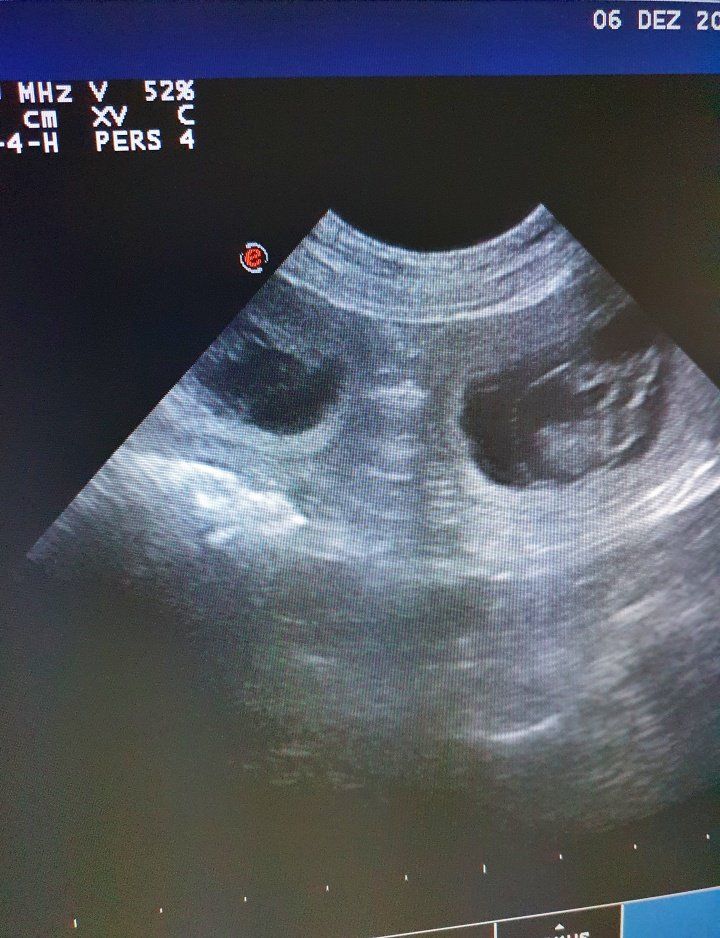

29 Tage später der spannende Tag

Das Ultraschall zaubert unseren Traum in die Wirklichkeit...kleine Miniminipudel mit kleinen Miniminiherzchen, die schon kräftig schlagen. Unsere Kelly wird wieder Mama und wir sind dankbar, glücklich und voller Vorfreude.